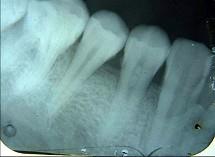

以下哪一项是诊断牙髓钙化的主要手段()A.光纤透照B.电活力测验C.视诊D.温度测验E.X线片检查

问题 以下哪一项是诊断牙髓钙化的主要手段()

选项 A.光纤透照 B.电活力测验 C.视诊 D.温度测验 E.X线片检查

答案 E